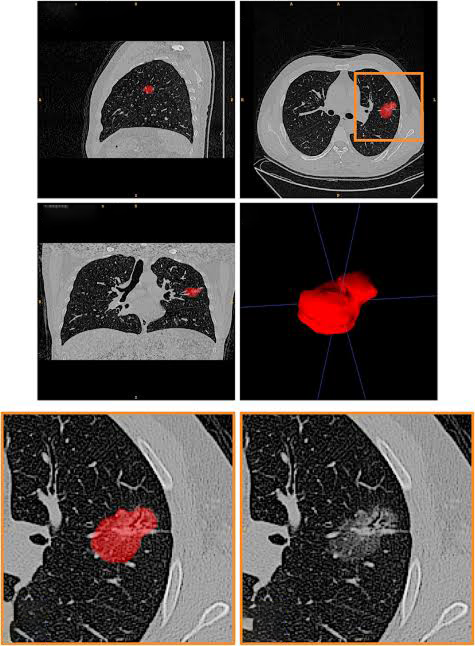

Pareidolia’s Role: We specialize in pixel-level annotation of nodules and abnormalities in chest CT scans. This training data enables AI models to differentiate between benign and malignant growths, making screening programs more accurate and cost-effective.

Radiomics extracts features like texture, intensity, and shape from CT and PET scans. AI models use these features to predict tumor type and aggressiveness.

Pareidolia’s Role: We provide detailed segmentation and 3D modeling of tumors, enabling radiomics-based AI systems to achieve higher diagnostic accuracy.